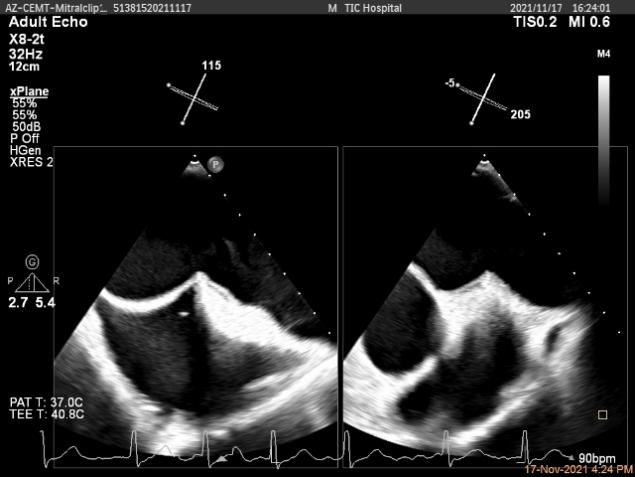

Multivue视图下将夹子正对AC区并调节Rotate

X-plane:下夹子尝试捕获靠近AC区脱垂瓣叶